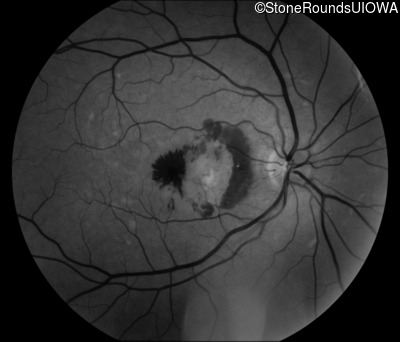

Age at visit: 59 years (Visit 3)

This 59 year old woman first noticed vision loss in her right eye a few months earlier. She has a cousin with Rhodopsin-associated RP.